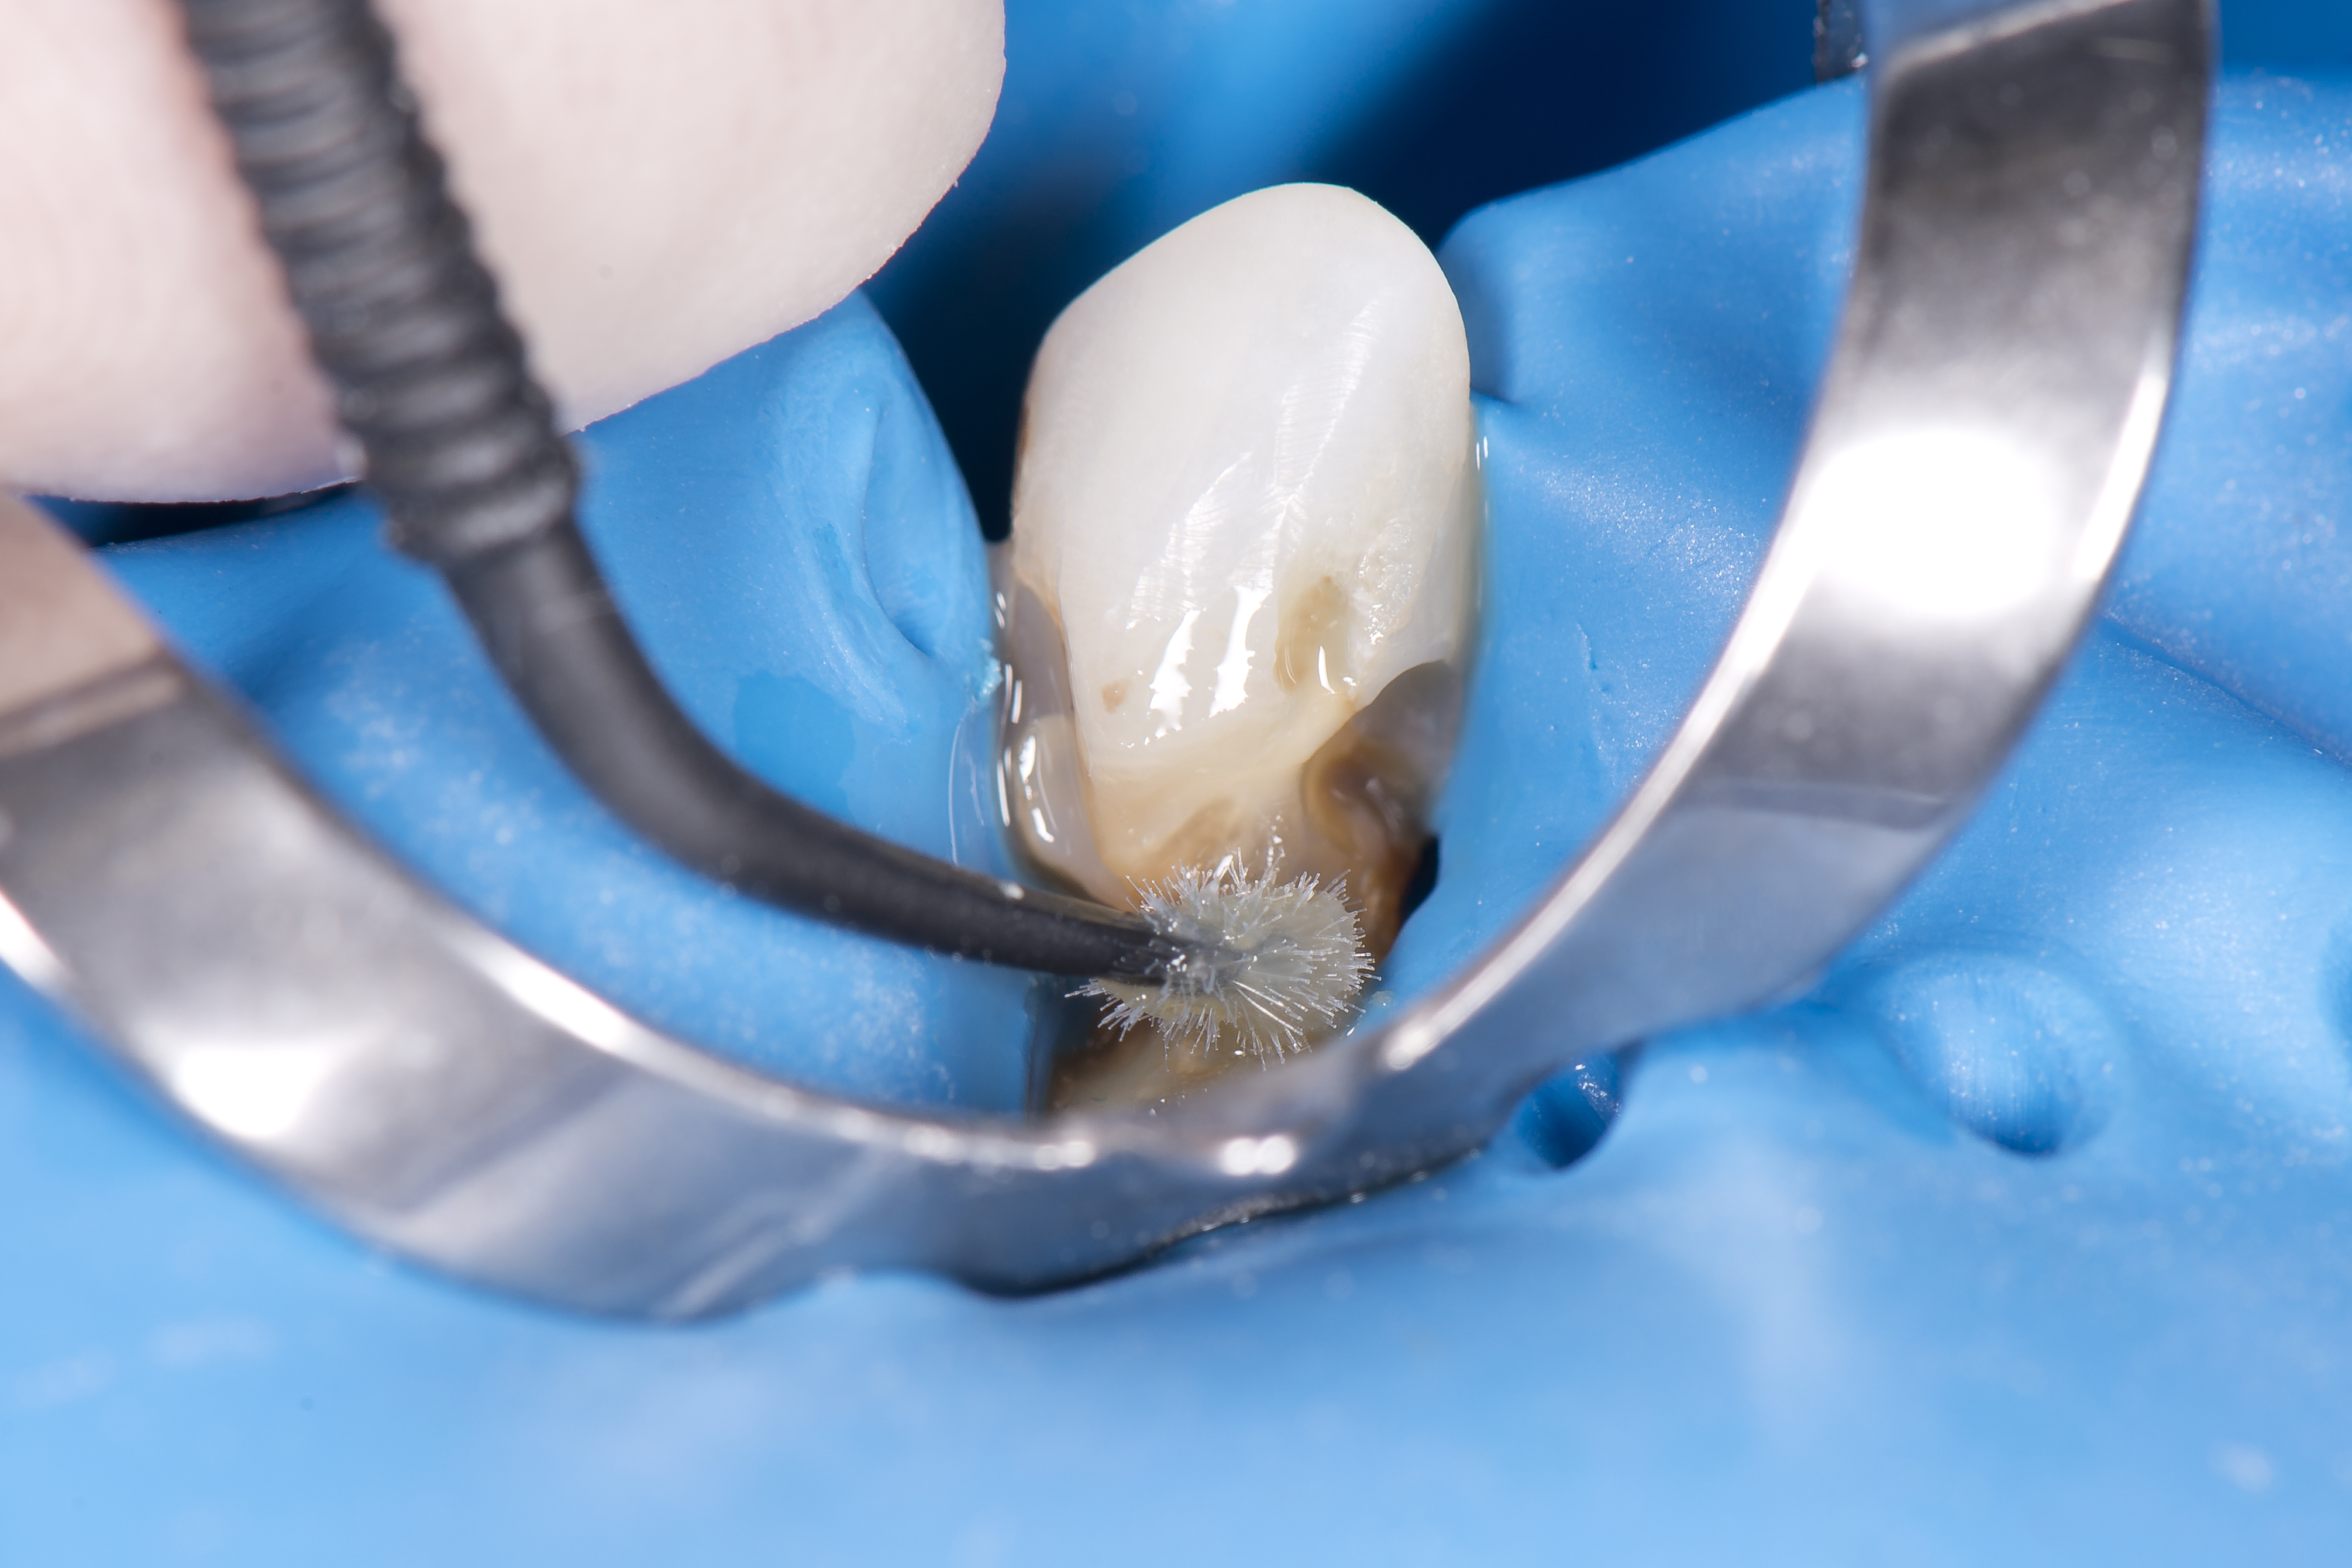

Ząb był izolowany przy pomocy koferdamu OptiDam (Kerr) i dokonano preparacji ubytku próchnicy pierwotnej lub też usunięto nieszczelne wypełnienie kompozytowe – w przypadku zębów 22 i 23 były to wypełnienia klasy V, pod którymi zaczęła rozwijać się próchnica okrężna obejmująca powierzchnię korony zęba i korzenia (ryc. 7).

Ryc. 7. Opracowywanie ubytku klasy V o charakterze próchnicy okrężnej w zębie 12.

Po opracowaniu ubytku dokonano wytrawienia selektywnego samego szkliwa kwasem ortofosforowym przez 15 sekund, który potem był wypłukiwany (ryc. 8).

Ryc. 8. Selektywne wytrawianie szkliwa jako wstęp do aplikacji uniwersalnego systemu łączącego OptiBond Universal (Kerr).

Z uwagi na charakterystykę ubytków, czyli dużą powierzchnię odsłoniętej zębiny, nie otoczonej szkliwem, zdecydowano się na zastosowanie systemu łączącego OptiBond Universal (Kerr). Jest to system samotrawiący, który można stosować zarówno w przypadku tkanek nie wytrawianych wcześniej, jak i poddanych trawieniu. Z tego powodu był on wcierany zarówno w powierzchnię zębiny (która nie była wcześniej wytrawiana), jak i w powierzchnię szkliwa przy pomocy microbrusha przez 20 sekund. Potem był poddawany polimeryzacji przez 10 sekund lampą LED Demi Plus (Kerr) (ryc. 9). Materiał OptiShade Medium (Kerr) był jedynym stosowanym materiałem i odcieniem w przypadku wszystkich ubytków (ryc. 10).

Ryc. 9. System łączący Optibond Universal (Kerr) był wcierany w zębinę i szkliwo przez 20 sekund.